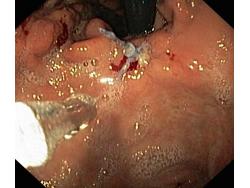

Krwawienie